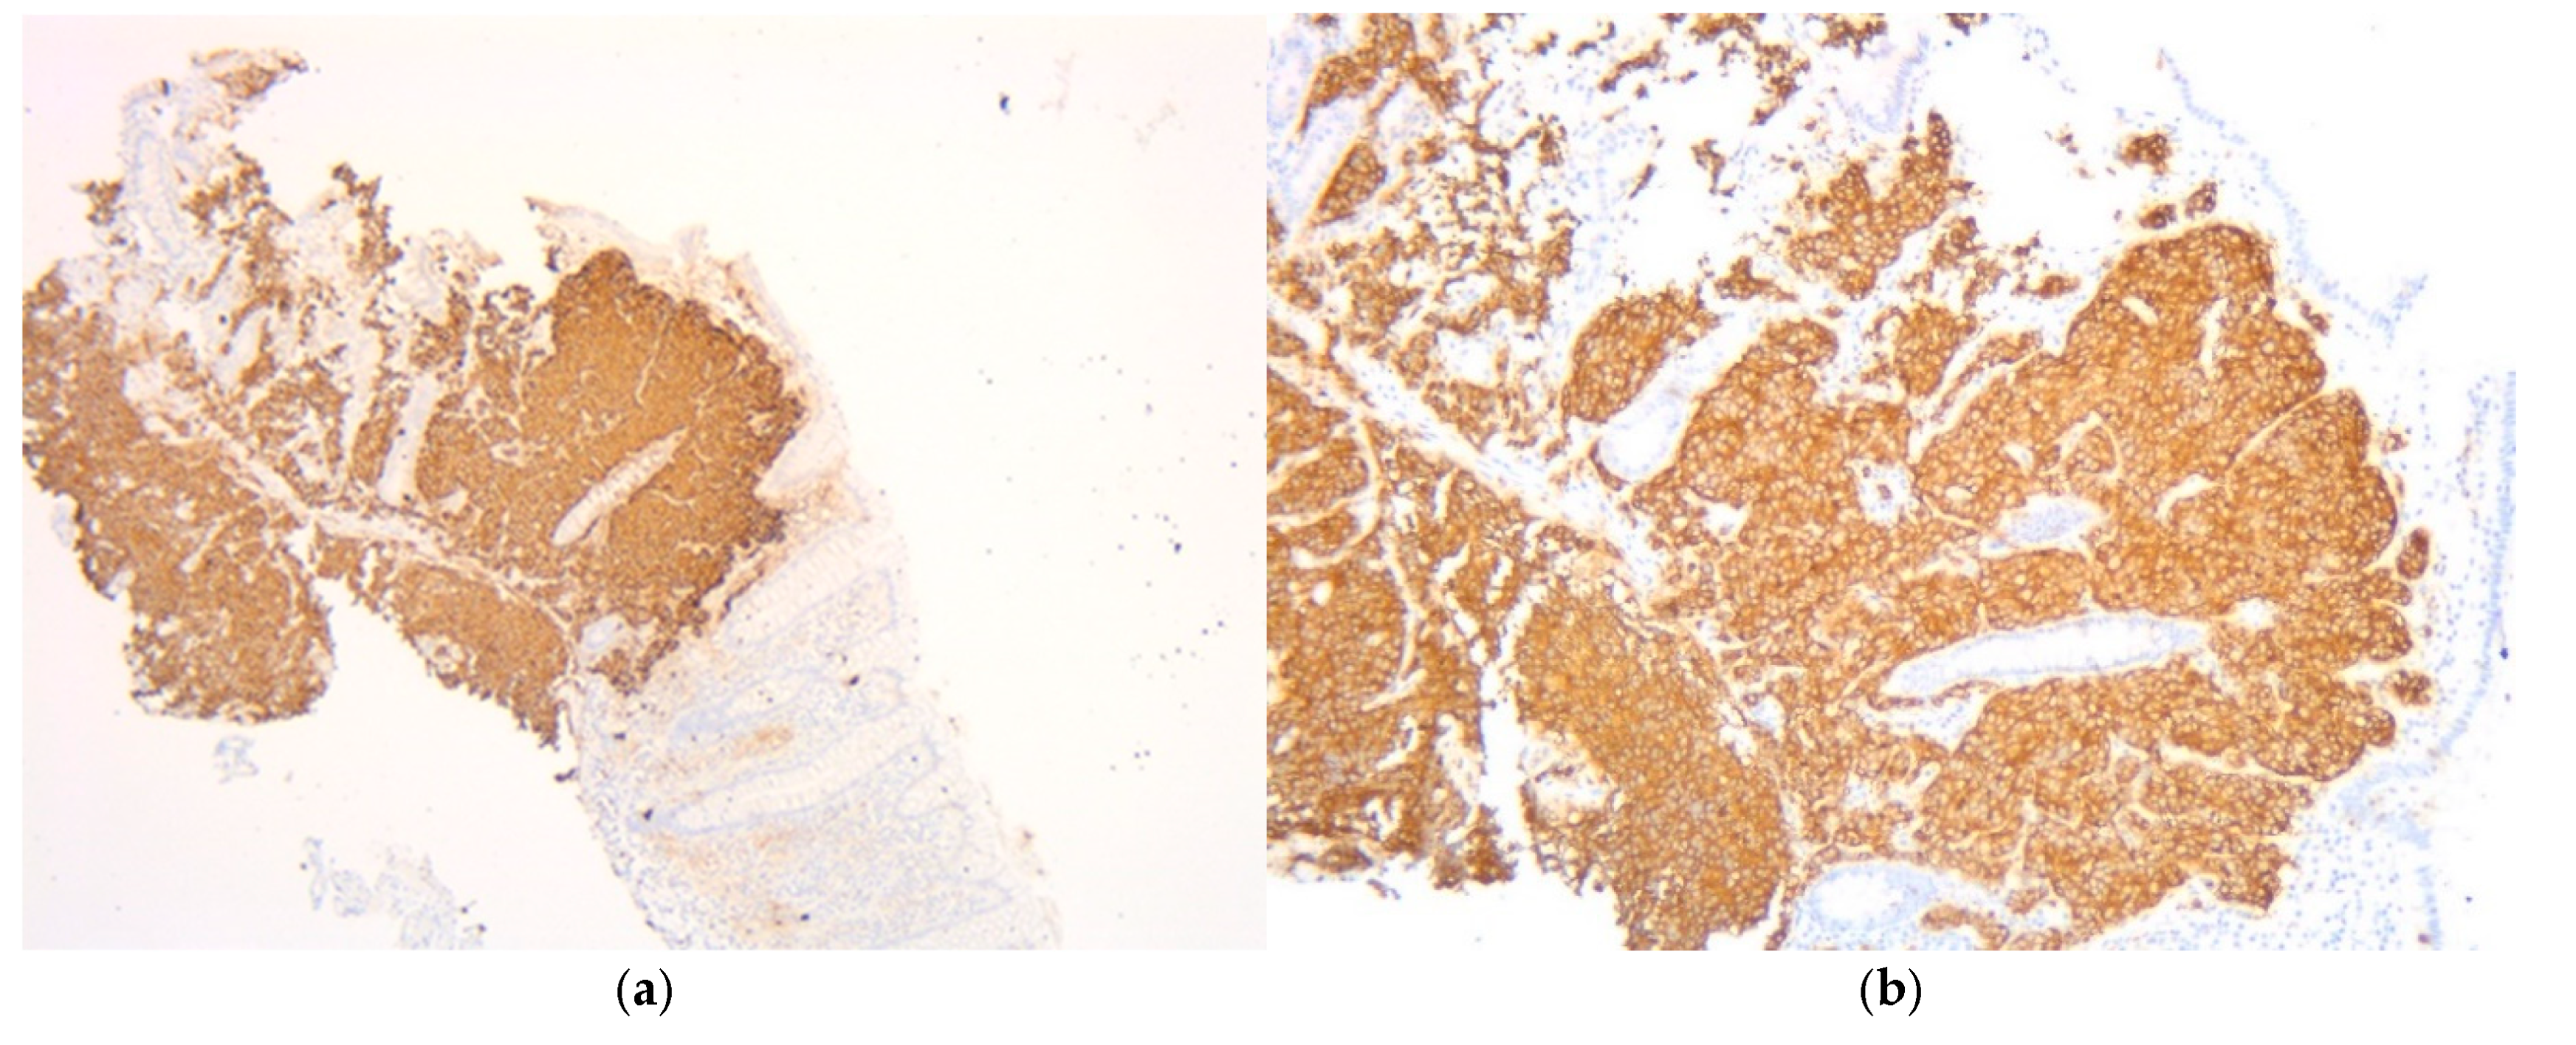

Figure 3.

Fragment of cecum mucosa. (a) Chromogranin (5×) intensely and diffusely positive cytoplasmic at the level of tumor cells. (b) Synaptophysin (10×) intensely and diffusely positive cytoplasmic at the level of tumor cells.

Following this diagnosis and given the presence of the mediastinal mass and multiple liver lesions, a percutaneous liver biopsy was performed to determine the origin of the metastatic disease. Histopathological examination of the liver specimen revealed tumor infiltration with an organoid and trabecular architecture, accompanied by a prominent fibro-hyaline stroma. The report noted “evident mitotic activity” and a Ki-67 proliferation index exceeding 25%. The immunohistochemical profile was decisive, demonstrating positive labeling for synaptophysin, CK7, and TTF-1 markers, while being negative for the hepatocyte marker HepPar1 and the intestinal marker CDX2. While a specific mitotic count and necrosis status were not quantified in the available liver biopsy report, the overall morphological features, high proliferative index, and immunohistochemical profile were conclusive. They confirmed the diagnosis of liver metastasis originating from a high-grade pulmonary neuroendocrine carcinoma, distinct from the cecal primary.